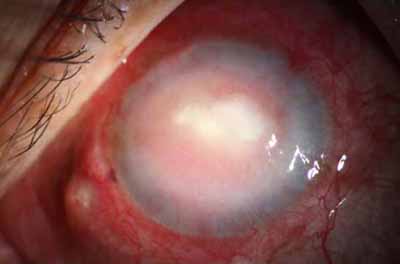

En su evolución se observará aumento del edema, aparición de un anillo inmunológico (Wessely), agrandamiento y coalescencia de los infiltrados que progresan hacia la formación de un absceso, queratolisis superficial, adelgazamiento y perforación corneal.

Cuando la invasión por Acanthamoebas es estromal, la respuesta celular tiene como consecuencia, que la abscesificación del estroma continuará aumentando a pesar del tratamiento….. y su resolución es lenta.

Ínício síntomas 6 meses - evolución catastrófica

Início síntomas 60 dias - No PL